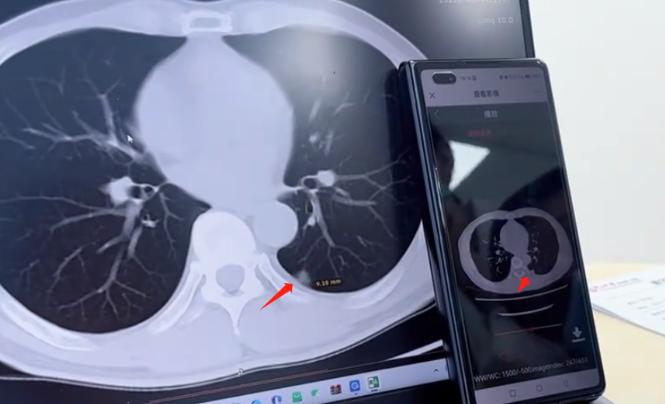

惊险!准备切除的肺结节是良性,藏在血管间的小疙瘩才是“真凶”......前阵子遇